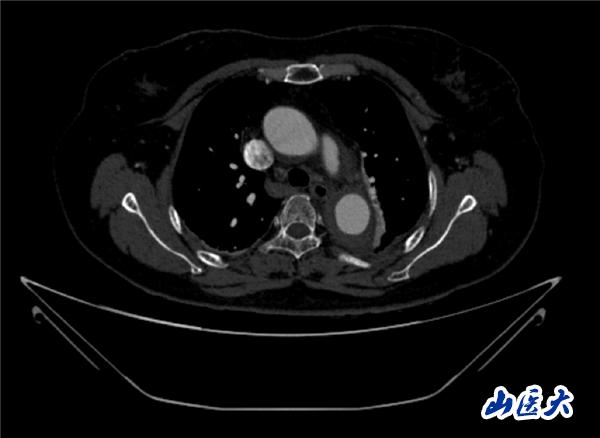

术前CTA

首例患者是一位55岁的女性,她患有高血压约2年时间,平时也会规律服用多种降压药,但血压控制始终不尽人意。2023年4月下午,她出现不明原因的头痛,在家拔罐缓解少许便未到医院就医,次日凌晨突感胸闷、胸背疼痛伴有呼吸困难等症状、家人急忙拨打了120,把患者送入医院急诊科进行救治,医生在急诊科行胸腹主动脉CTA时,显示主动脉弓部-降主动脉及腹主动脉壁间血肿,遂收治入医院血管外科,患者入院10天后复查血肿仍未有改善,依然伴有胸背部疼痛等不适,如不进一步处理,可能发展为夹层危及生命,患者及家属经过与医生团队了解沟通,决定进行创伤小、恢复快的介入手术治疗。张玮教授、符伟国教授、董红霖教授及其血管外科团队(闫盛、常文凯、田琴琴)共同商讨手术方案,最终确定使用Zipper™一体式主动脉弓覆膜支架系统,行胸主动脉覆膜支架腔内隔绝术+无名动脉、左颈总动脉、左锁骨下动脉分支重建术为患者进行治疗。董红霖教授及其血管外科团队根据患者术前头颅CT平扫提示双侧侧脑室旁缺血灶,血压控制不稳定,属夹层壁间血肿非典型夹层等风险点,制定了完整的手术方案,术中经股动脉置入Zipper支架主体,经预留导丝超选无名动脉,并确保主体支架对位准确,顺利置入左颈总动脉、左锁骨下动脉支架,重建弓上三分支。手术过程非常顺利。术后观察主动脉及分支覆膜支架定位准确;无内漏;分支支架通畅,动脉供血正常。